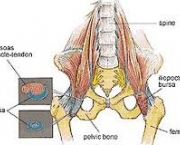

A bursite Trocanteriana é uma inflamação em uma ou mais bursas encontradas na articulação do quadril. Esta bursite pode ser causada por uma queda ou golpes ao lado do quadril, atrito associado a uso excessivo, pé pronado ou fraqueza de glúteo médio.